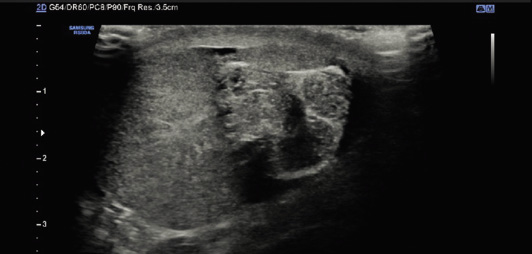

• Ecografía-doppler testicular bilateral: se valora la simetría en relación al tamaño, localización, aspecto del parénquima testicular y la presencia o no de flujo doppler arterial. Ofrece también información sobre: el engrosamiento y posición del cordón espermático (torsión), engrosamiento de cubiertas testiculares y de la bolsa escrotal, o tamaño y signos inflamatorios de los apéndices testiculares o del epidídimo(2,11,14) (Figs. 4 y 5).

Figura 4. Ecografía-doppler testicular: torsión de testículo izquierdo.

A. Testículo derecho normal, con preservación del flujo arterial.

B. Torsión de testículo izquierdo, aumentado de tamaño, sin flujo vascular arterial.

C. Ecografía de testículo izquierdo en el que se visualiza la vuelta de torsión del cordón espermático.

Ofrece una sensibilidad del 65-100%, con una especificidad en torno al 75-100%, un valor predictivo positivo del 100% y negativo del 98%(3,14-16). Característicamente, el flujo arterial está disminuido o no se evidencia en el testículo torsionado; pero es fundamental tener en cuenta algunas consideraciones que pueden llevar a errores diagnósticos. Así, debido al propio proceso inflamatorio, es posible evidenciar: aumento de flujo venoso por congestión testicular, hipervascularización de las cubiertas testiculares o preservación parcial de la vascularización arterial en las fases iniciales de torsión testicular o en las torsiones intermitentes, lo que puede dar lugar a resultados falsos negativos. Por todo esto, y sumado a que la ecografía es una prueba operador-dependiente, se debe indicar la exploración testicular mediante intervención quirúrgica, siempre que exista la sospecha clínica de torsión testicular, a pesar de que el estudio doppler informe sobre la presencia de flujo testicular.